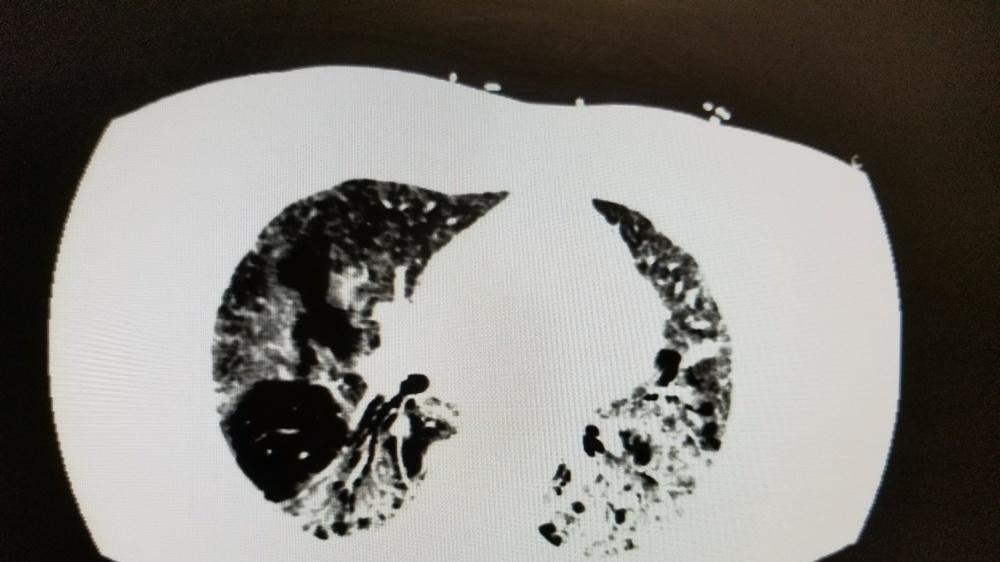

- 87%的肺癌病例可归因于烟草暴露,长期被动吸烟也要小心肺癌